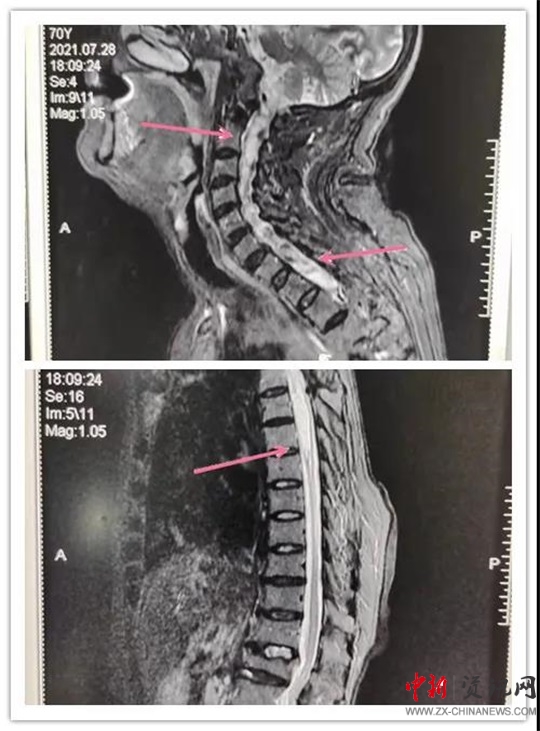

患者,女,70歲,六年前患脊髓空洞癥在某醫(yī)院行“脊髓空洞蛛網(wǎng)膜下腔分流手術(shù)”后病情好轉(zhuǎn)。近段時間,因“后肩部疼痛,無痛溫覺喪失,雙下肢疼痛、無力逐漸加重”癥狀加重,來汝南縣人民醫(yī)院就診,行MR檢查診斷為“頸胸脊髓空洞”。神經(jīng)外科副主任沈明輝認真研究了患者的病情和 MR片子,認為手術(shù)可行,隨即收住患者到科室;颊呷朐汉,完善了術(shù)前檢查,由于患者年事已高,患有高血壓、心臟病等疾病,使病情更加復(fù)雜,手術(shù)難度風險進一步加大。手術(shù)團隊組織了全科會診,對患者手術(shù)情怳進行了分析。如果不做手術(shù),病情進一步發(fā)展,患者雙下肢會截癱,再做手術(shù)也很難恢復(fù)。在得到患者家屬的理解和支持后,根據(jù)患者的病情,手術(shù)團隊反復(fù)討論術(shù)中可能出現(xiàn)的問題:完善圍手術(shù)期應(yīng)急預(yù)案,制定精準的治療及手術(shù)方案,擇期為患者成功實施了“頸胸脊髓空洞胸腔引流”手術(shù)。術(shù)后患者雙下肢肌力明顯好轉(zhuǎn),正在康復(fù)中。

手術(shù)前